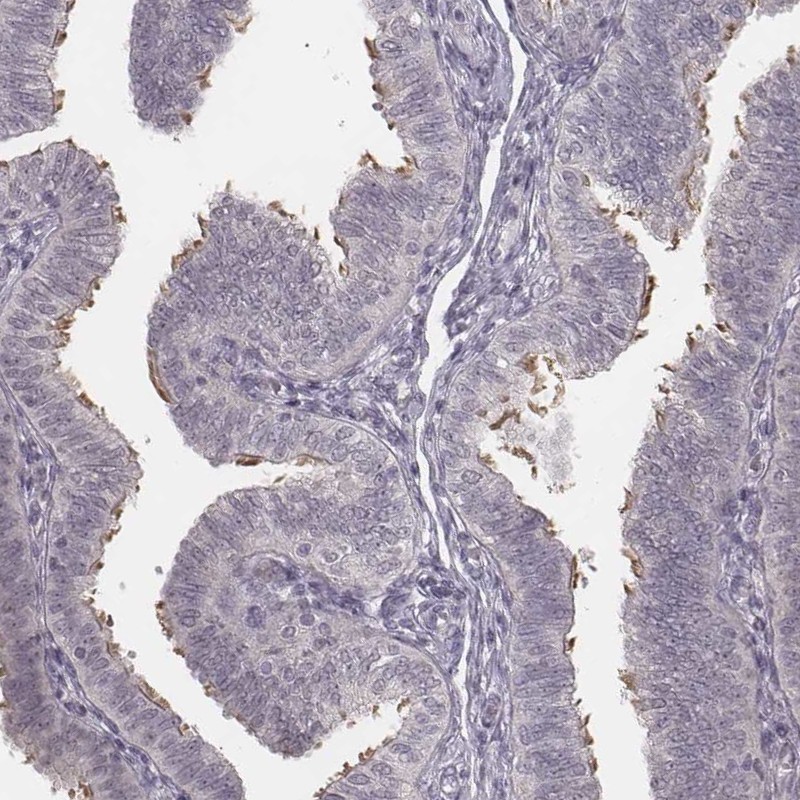

Immunohistochemistry analysis in human fallopian tube and duodenum tissues using Anti-IQCG antibody. Corresponding IQCG RNA-seq data are presented for the same tissues.